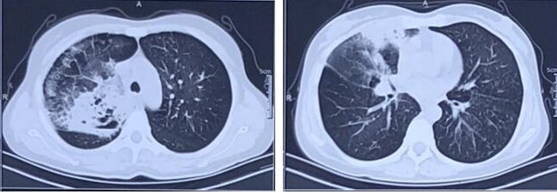

第10天复查胸部CT:右肺上叶空洞较前明显吸收,右肺中叶实变较前缩小(图3)。虽然患者呼吸困难明显减轻,肺部病变明显吸收,但复查CEA水平继续升高,遂行CT引导下肺穿刺活检并复查胸部CT(图4),病理回报光镜下可见梭形细胞增生,纤维组织增生伴慢性炎,间质呈机化性改变。鉴于临床症状、实验室检查及肺部影像学改善,考虑肺部感染的经验性治疗有效,遂安排转回当地治疗。

图片

图3  患者胸部CT

图4  患者胸部CT